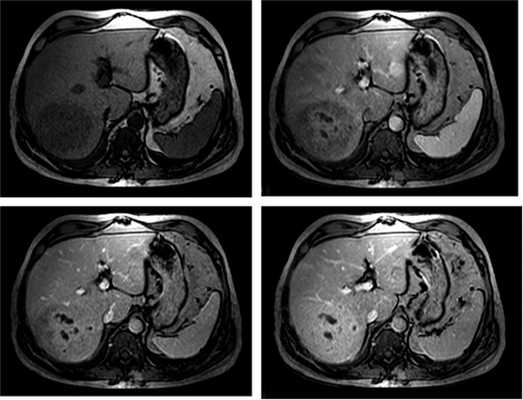

При контрастном усилении отмечено накопление контрастного вещества в артериальную фазу центробежно, с наибольшей локализацией контрастного агента в центральной части (рис. 3). Рисунок 3. Магнитно-резонансная томограмма с контрастированием (нативное исследование, 15 с - артериальная фаза, 60 с - венозная фаза, более 4,5 мин - отсроченная фаза). К отсроченной фазе образование набирает контрастный препарат всем объемом, довольно гомогенно и по отношению к паренхиме печени - слабогиперинтенсивно. При этом в центральной части свободными от контрастного средства во все фазы исследования остаются жидкостные участки.